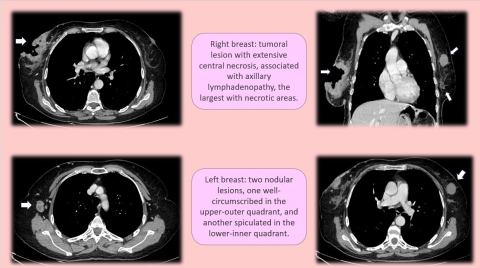

Invasive Breast Carcinomas: 3 interesting cases

Histopathological analysis ultimately revealed two cases of invasive ductal carcinoma (IDC) and one case of invasive lobular carcinoma (ILC), representing the most common and second most common subtypes of invasive breast malignancy, respectively.

In the first of these cases, the patient’s contrast‑enhanced CT showed bilateral spiculated masses with heterogeneous enhancement within both breasts, accompanied by regional lymphadenopathy, peritoneal carcinomatosis, and multiple hepatic lesions. These findings indicated advanced systemic dissemination at first presentation, a scenario that underscores the power of CT to detect both primary malignancy and distant spread in a single examination. Subsequent targeted breast imaging and biopsy confirmed high‑grade invasive ductal carcinoma in both breasts.

The second IDC case involved a unilateral enhancing breast mass with associated ipsilateral axillary lymphadenopathy, without evidence of distant metastatic disease. The radiologic appearance was consistent with invasive ductal carcinoma, and histopathology confirmed the diagnosis following directed biopsy.

Fig 2.jpg

CT and Histology Highlights:

• Bilateral IDC: spiculated enhancing masses, regional lymphadenopathy, peritoneal carcinomatosis, hepatic metastases

• Unilateral IDC: enhancing mass with ipsilateral lymphadenopathy, no distant metastases

• Biopsy confirmed all three invasive breast malignancies

• CT demonstrated capability to detect both primary tumors and advanced metastatic disease